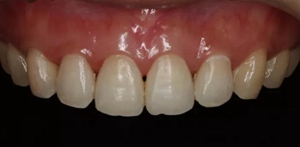

術后顯示,滲透樹脂恢復了天然牙釉質(zhì)的折光率(天然通透牙釉質(zhì)折光率1.62滲透樹脂折光率是1.52)顯的很自然,很有光澤。完全是天然牙質(zhì)的顏色。

(下圖是拋光完成)

治療完成的上頜牙齒和未治療的下頜牙齒形成明顯對比。

治療前和治療后的對比,患者很高興很滿意。